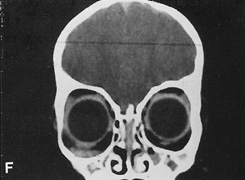

Fig. 14. A,B. Large intraorbital lymphangioma causing proptosis and optic nerve compression

in a 2-year-old child. C. View of the left orbit from above after removal of the frontal bone flap, including

the supraorbital rim and orbital roof. An extensive exposure

of the entire superior and lateral orbit is afforded. The levator

and superior rectus complex is being retracted laterally with a muscle

hook, whereas the Freer elevator retracts the superior oblique muscle

medially. The frontal nerve can be seen running from posterior to anterior

over the superior orbit. The orbital mass is exposed in this fashion. D. The fronto-orbital bone flap is wired back in place after completion of

the procedure. E. Postoperative appearance of the patient. F. The postoperative CT scan shows complete removal of the lymphangioma. This

large and diffuse lesion would have been difficult to remove with